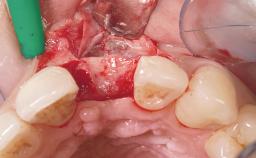

Immediate Placement of an Implant in a Maxillary Right Central Incisor Site

A 30-year-old female patient was referred to the office for the treatment of tooth 11. Her chief concern at the initial visit was to inquire, “Why is my tooth pink?” Upon clinical examination, it was determined that tooth 11 had a previous history of trauma and that the clinical crown had become noticeably pink in color as a result of internal resorption. This diagnosis was confirmed radiographically, indicating a large radiolucency involving the central and distal portions of the clinical crown. It was determined that restoration of this tooth was not possible, and that extraction was indicated. The presence of a mid-line diastema, which the patient wanted to reproduce, directed the treatment plan for tooth replacement utilizing a dental implant.

Bone Augmentation Horizontal|Simultaneous

Augmentation Materials Autogenous chips|Membrane

Socket Integrity Sufficient, with intact bone walls

Bone Volume Sufficient, with intact walls